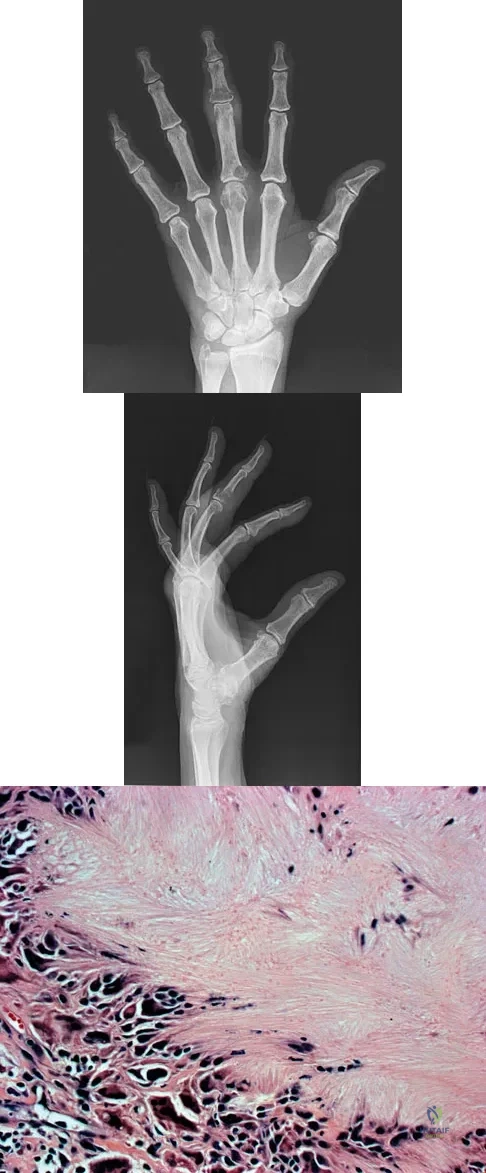

Question 30

A 25-year-old man has a mass on the medial aspect of the left knee. He reports that the mass has been present for several years, but a recent increase in physical activity has resulted in periodic tenderness. Radiographs are shown in Figures 13a and 13b. What is the most likely diagnosis?

Explanation